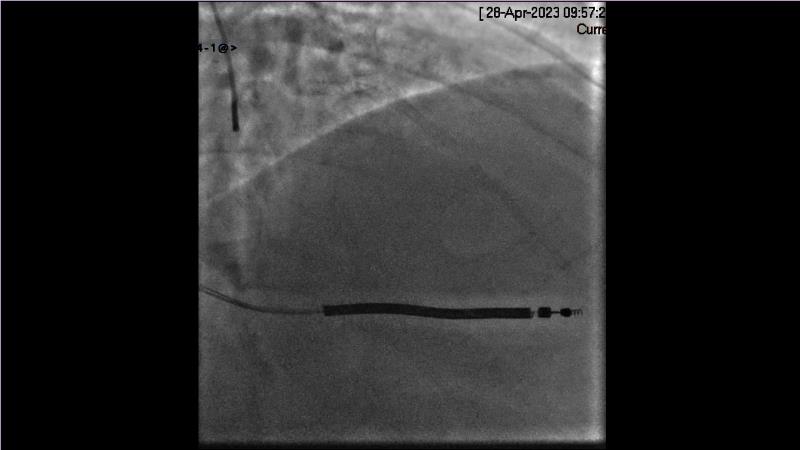

- To learn from the real world registries and complex cases to understand the practical implications and potential of the device in diverse patient population